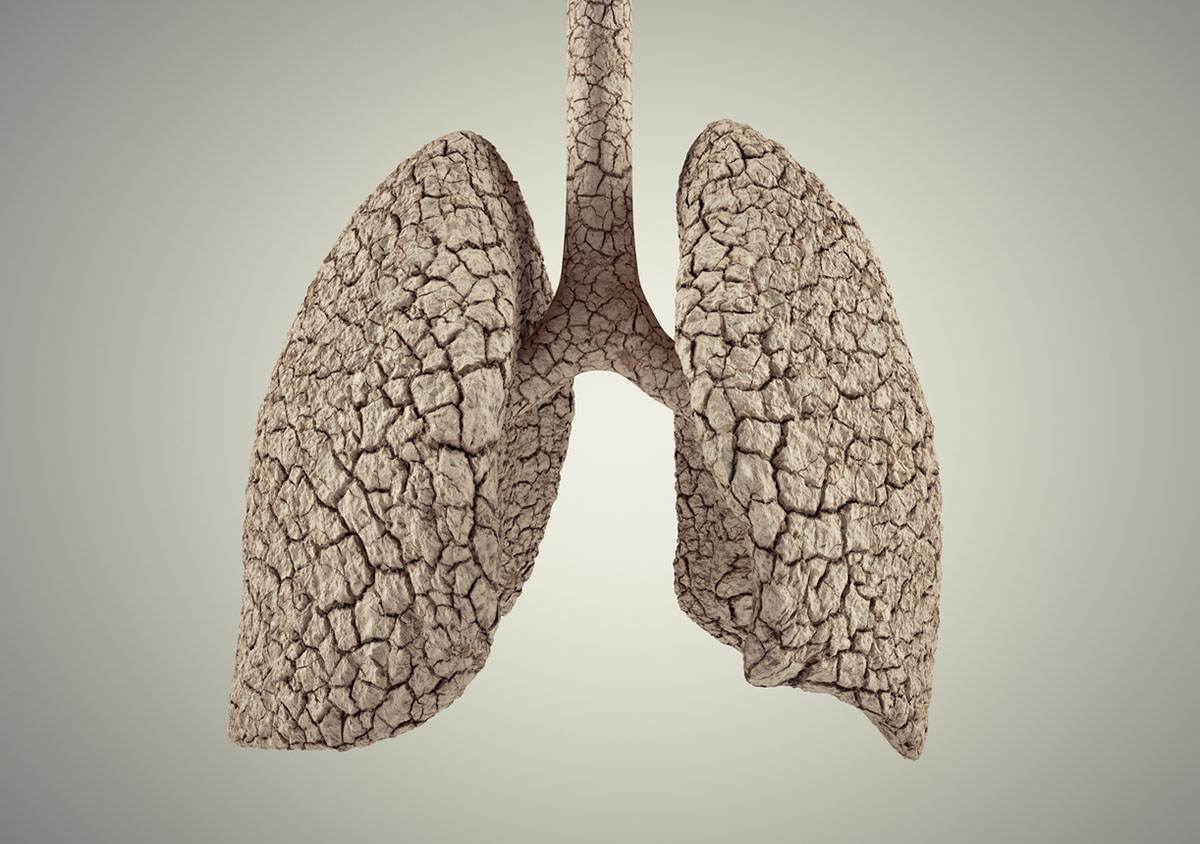

Ενώ η λειτουργία των πνευμόνων συνήθως βελτιώνεται μετά τη διακοπή του καπνίσματος, ενδέχεται να εμφανιστεί επίμονος βήχας ή δύσπνοια αρκετό καιρό αφού διακόψετε το κάπνισμα. Αυτό μπορεί να οφείλεται στο ότι οι πνεύμονες «καθαρίζουν» τα συσσωρευμένα υπολείμματα ή επουλώνονται από την προηγούμενη έκθεση στον καπνό.